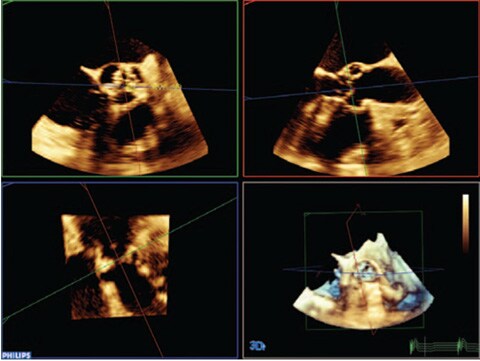

Introducing HeartModelᴬ⋅ᴵ⋅, a new Anatomically Intelligent Ultrasound (AIUS) application that brings advanced Live 3D quantification, automated 2D views and robust reproducibility to echocardiography. HeartModelᴬ⋅ᴵ⋅ automatically detects, segments, and quantifies the LA (Left Atrium) and LV (Left Ventricle) from a 3D volume.

This study compared quantification between 2D and Live 3D HeartModelᴬ⋅ᴵ⋅ and demonstrated a 82% timesavings for HeartModelᴬ⋅ᴵ⋅ when using the automated capability, and 71% timesavings when minor edits were required.